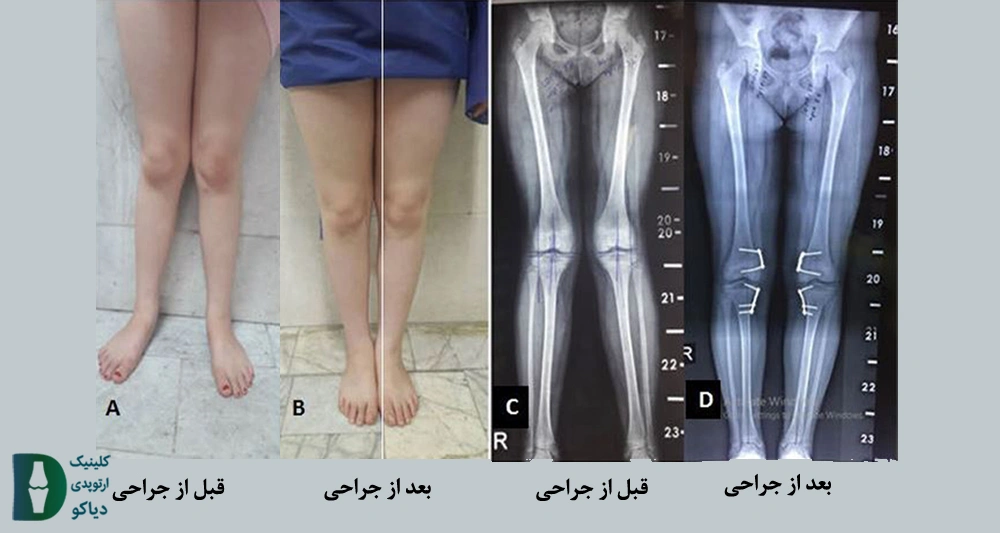

در شکل زیر تصویری از قبل و بعد از جراحی هدایت رشد نمایش داده شده است:

در تصویر زیر قبل و بعد از جراحی استئوتومی در یک نوجوان به نمایش در آمده است:

همانطور که گفته شد این جراحی میتواند موجب اصلاح فرم زانو شود. در شکل زیر نمونه ای موفق از جراحی استئوتومی به نمایش درآمده است: